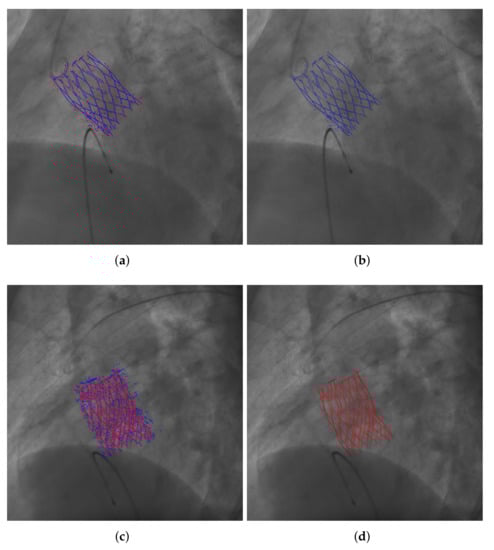

3.1. Image Acquisition and Annotation